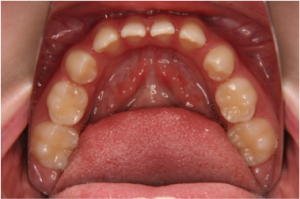

先天欠如歯で最も多いのは下顎の第2小臼歯(6歳臼歯の前の歯)です(図1)。

図1:下顎第2小臼歯の両側性先天欠如

乳歯の後から生えてくる永久歯がない